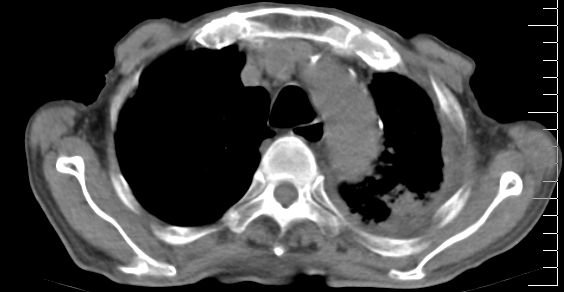

标题: CT10141:男、84岁,咳嗽、咯血1年。 [打印本页]

标题: CT10141:男、84岁,咳嗽、咯血1年。

1左侧胸腔积液并包裹2心包积液3左下肺癌?建议支纤镜检。

支持左侧中央型肺癌伴下叶肺不张\\纵隔淋巴结转移.左侧包裹性胸腔积液\\心包积液.左侧少量胸腔积液..慢性支气管炎伴部分间质纤维化.

支持:左侧中央型肺癌伴下叶肺不张\\纵隔淋巴结转移.左侧包裹性胸腔积液\\心包积液.左侧少量胸腔积液..慢性支气管炎伴部分间质纤维化.另:支气管分支根部明显阻塞 狭窄,内膜凸凹不平,提示内膜增生物。

左肺中心性肺癌并肺不张,同侧 胸膜及心包转移,左肺癌性淋巴管炎

左侧中心型肺癌,左侧胸腔积液部分包裹,心包积液,肿膈淋巴结显示。

左侧中央型肺癌伴下叶肺不张\\纵隔淋巴结转移.左侧包裹性胸腔积液\\心包积液.左侧少量胸腔积液..慢性支气管炎伴部分间质纤维化

咯血病史较长,左肺下叶实变,体积未明显缩小,隐约可见血管影及坏死阴影,双肺门及纵隔淋巴结增大,心包增厚积液,纵隔右移位,单侧胸腔积液,首先考虑:大叶型肺泡癌伴纵隔心包转移。

左下中央型肺癌伴阻塞性不张,肺炎,左侧包裹性胸腔积液\\心包积液

左肺中心性肺癌并左肺下叶肺不张,纵隔淋巴转移、同侧胸腔及心包积液(转移)。